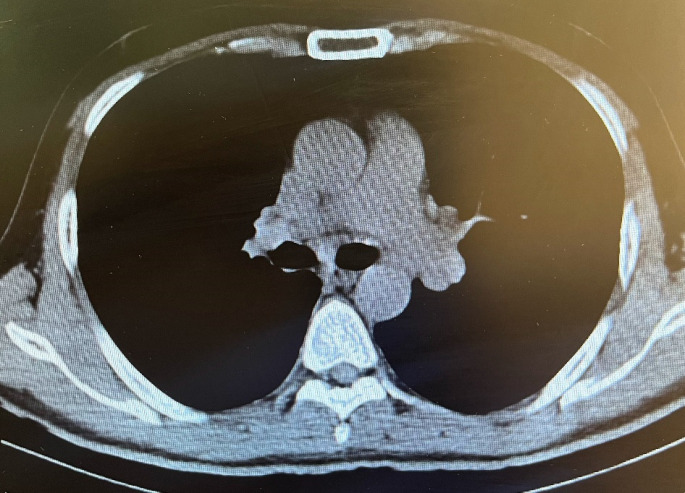

Sarcoidosis is a challenging disease characterized by the formation of granulomas in multiple organs. It presents with a variety of clinical symptoms, making diagnosis difficult for physicians. Myocardial involvement in sarcoidosis is rare, but it worsens prognosis and can lead to mortality. Physicians face challenges in diagnosing cardiac sarcoidosis due to its wide range of symptoms. Cardiac sarcoidosis that affects only the heart without involvement of other organs is extremely uncommon. In this case, we examine the scenario of a middle-aged man who experienced palpitations and was diagnosed with ventricular tachycardia. He remained in stable condition without any other clinical signs suggestive of sarcoidosis. This case highlights the importance of considering sarcoidosis as a potential diagnosis in patients presenting with palpitations and ventricular tachycardia on electrocardiogram, particularly when these symptoms are accompanied by sudden new-onset systolic dysfunction despite normal coronary arteries.